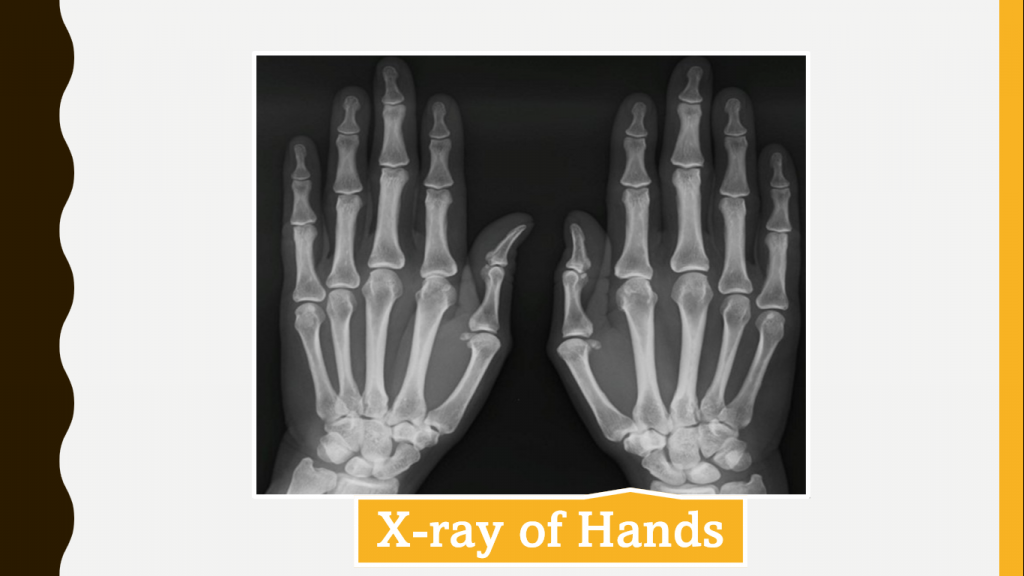

She had no significant wrist stiffness and limitation of movements of knees. Inflammatory parameters were normal and radiography of both hands and knees showed grade 3 osteoarthritis changes. The other diagnoses to be considered are rheumatoid arthritis and seronegative spondyloarthropathy.

As per ACR criteria (Table 1) for diagnosing osteoarthritis (OA) of the knee, the age of the patient is generally 50 years, but there is no age specification for hand OA (Table 2). The current patient had symptoms since the age of 37 and the joints involved were the knees and ankles. The pain had recently progressed to elbows and shoulders. The X-ray of knee joints was suggestive of radiological features of OA. The involvement of elbows and shoulders in OA is rare, hence the possibility of RA should be considered. The inflammatory parameters could be normal in the early stages of RA or with very low disease activity. To confirm the diagnosis, the patient was evaluated for anti-CCP and the result was negative. In India, the onset of OA is early and has been reported even in youngsters of ≤40 years of age. The patient is an agriculture labourer and the postures of work include cross-leg and squatting, the chance of OA is higher and occurs at an early age.

The patient's inflammatory parameters were normal, and the stiffness also did not qualify for inflammatory arthritis. In India, the incidence of OA is noted in younger patients and in such patients, all the parameters including anti-CCP may appear normal. In such cases, the possibility of OA primary should be considered. Since the patient had symptoms on both knee and hand joints, primary rather than secondary OA should be considered. Moreover, the agricultural occupation would have caused secondary stress on the joints. Early-onset and involvement of DIP indicate the primary variant of OA.